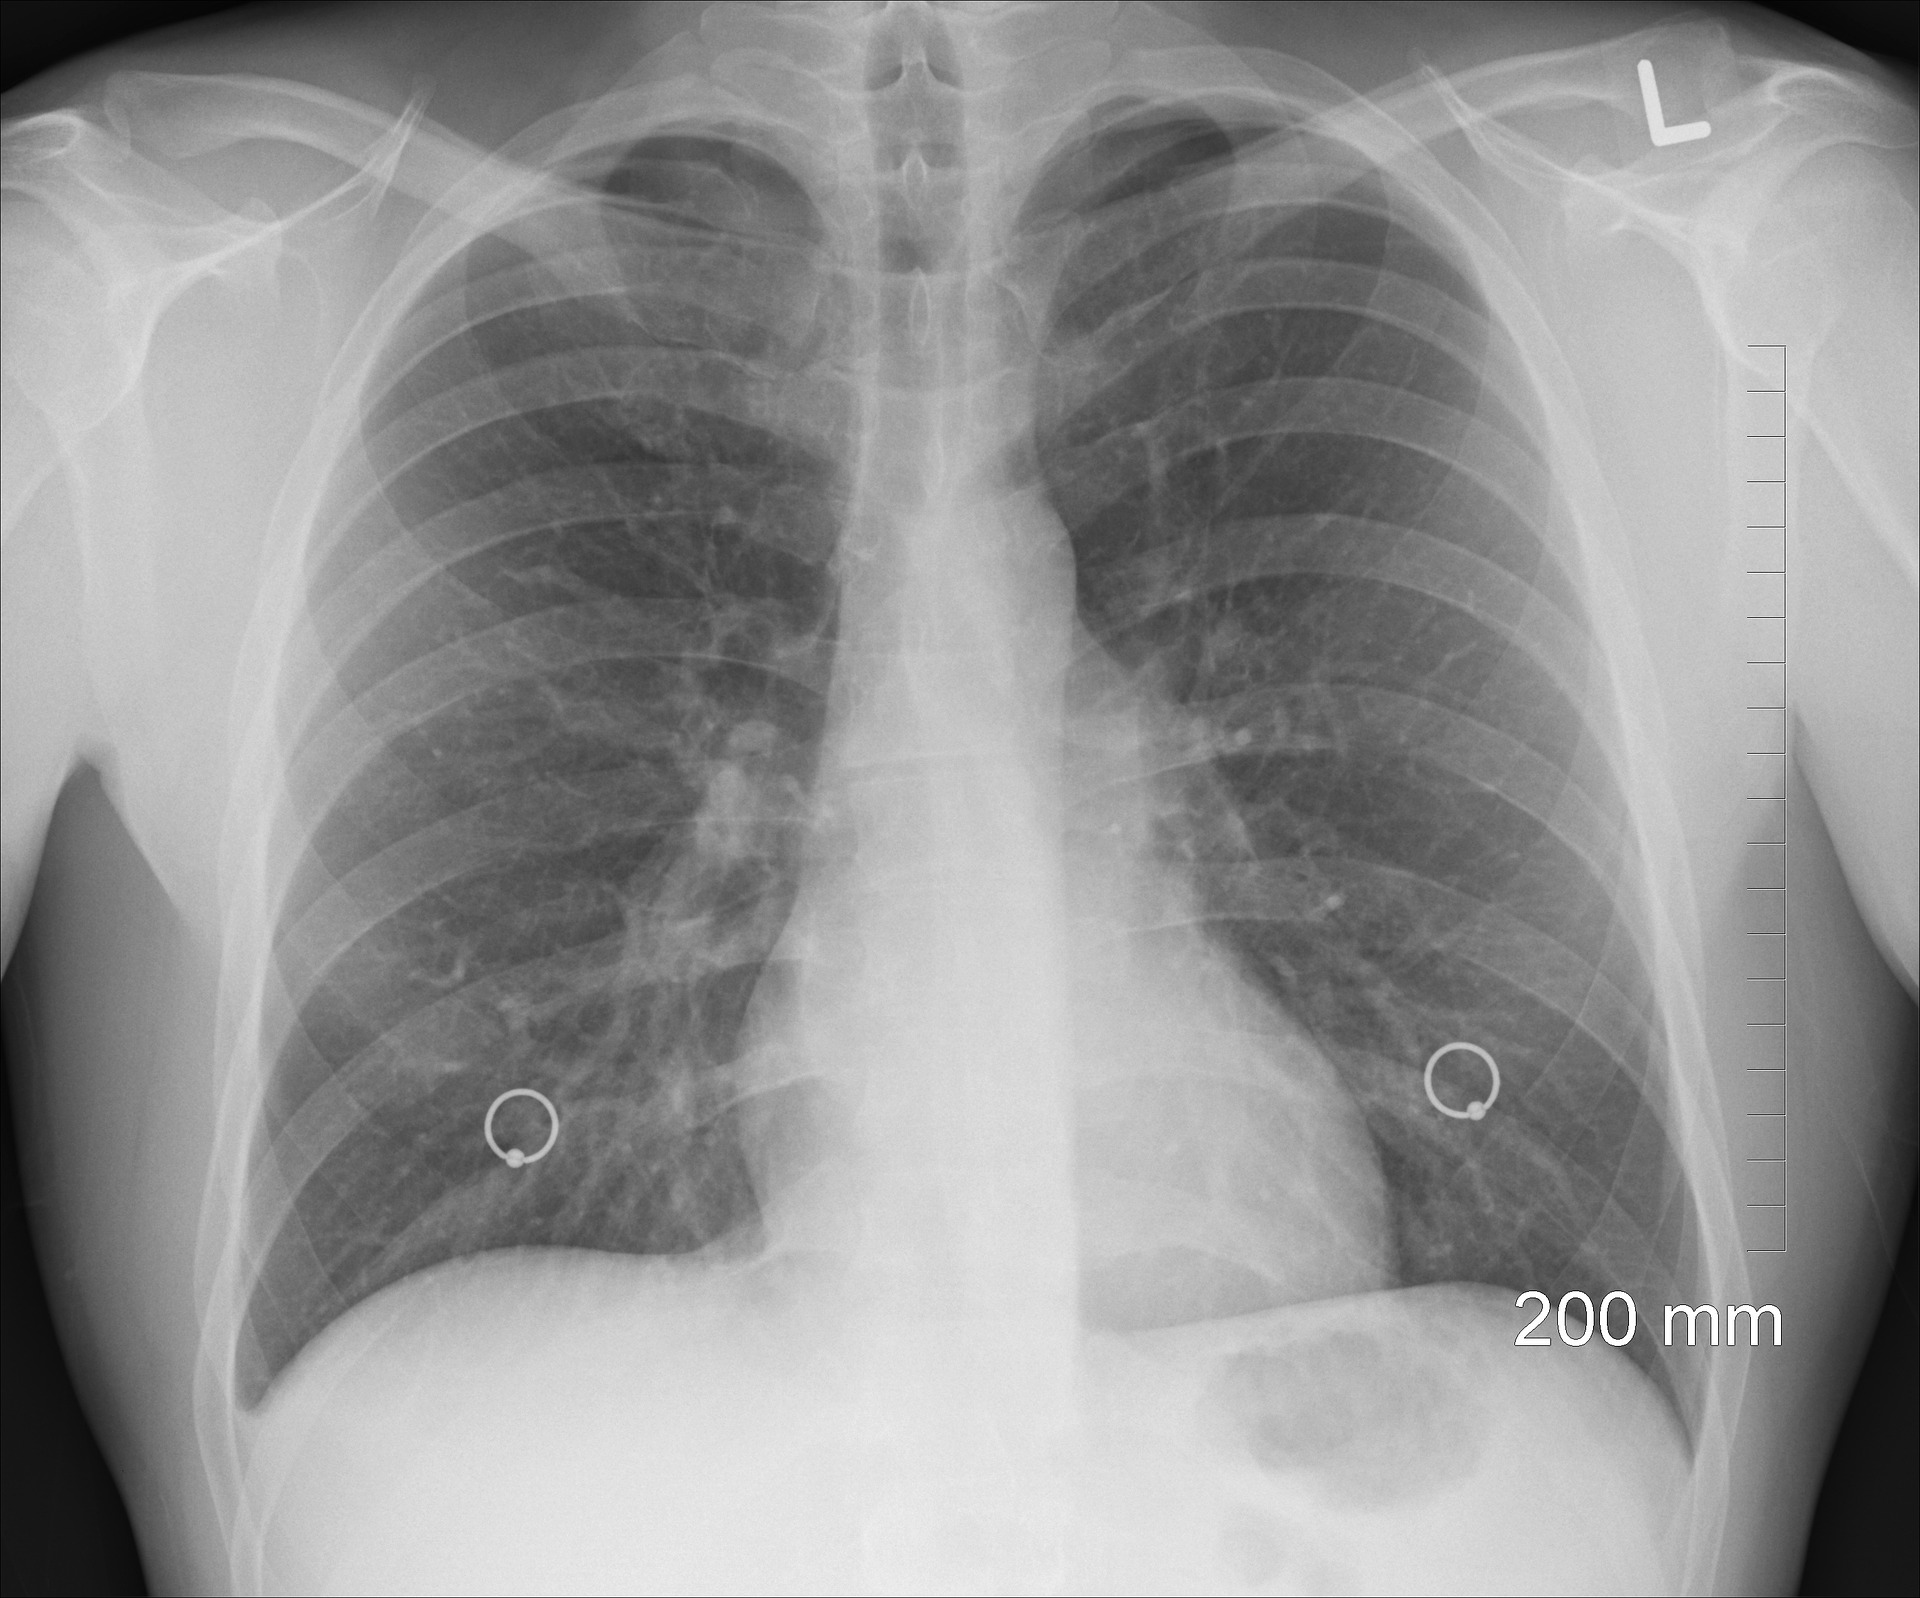

Chest X-Ray